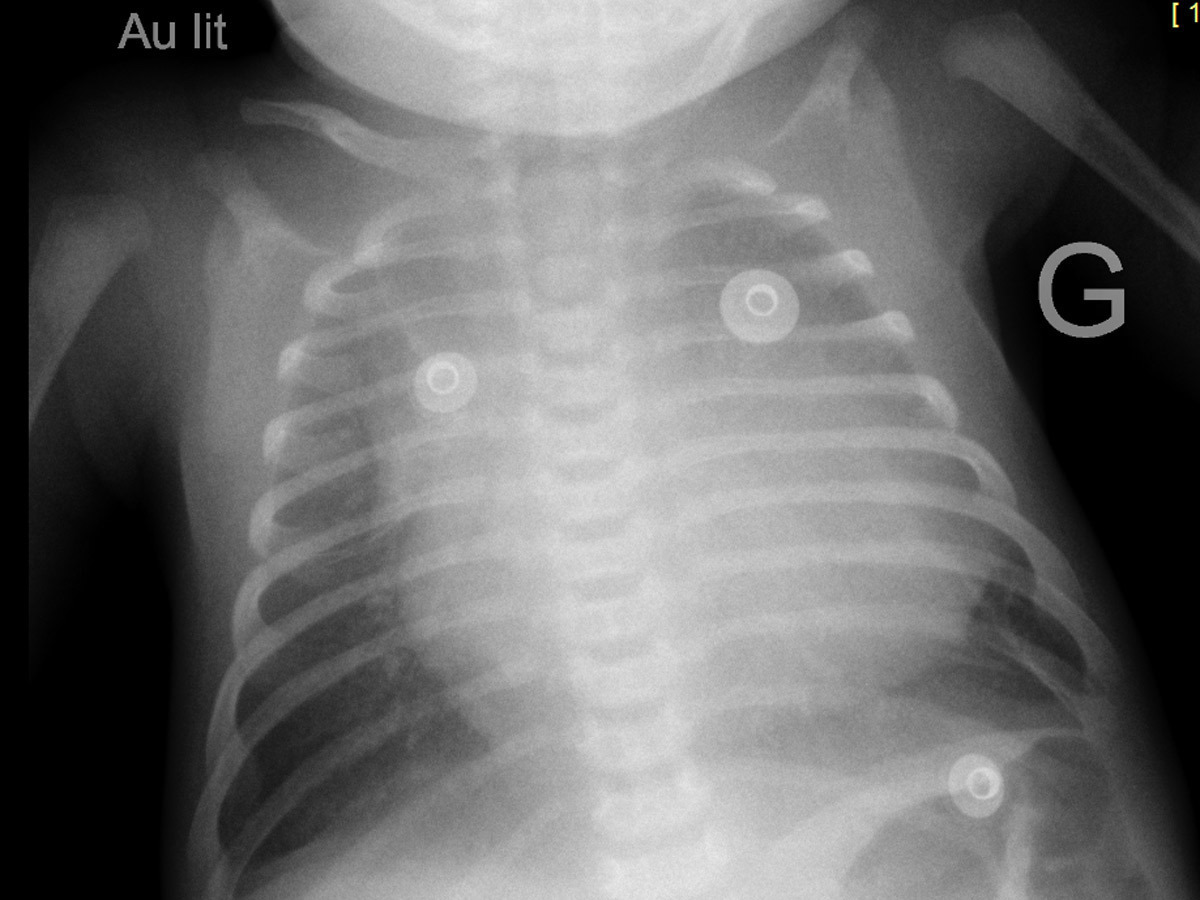

À l’examen clinique ce jour, vous notez : poids 2 800 g, taille 46 cm, PC 35 cm. Fréquence cardiaque 145/mn, fréquence respiratoire 25/mn. Enfant rose, temps de recoloration cutanée 1 seconde, pas de marbrures, extrémités chaudes. Bruits du cœur réguliers, pas de souffle cardiaque audible, pouls fémoraux et huméraux perçus. Murmure vésiculaire bilatéral et symétrique, pas de bruit surajouté. Enfant eupnéique. Abdomen souple, pas d’hépatomégalie. Bon tonus axial et périphérique. Fontanelle normotendue. Reste de l’examen sans particularité.

Certaines cardiopathies ne soufflent pas, d’autres soufflent plus tardivement (communication interventriculaire [CIV] par exemple)